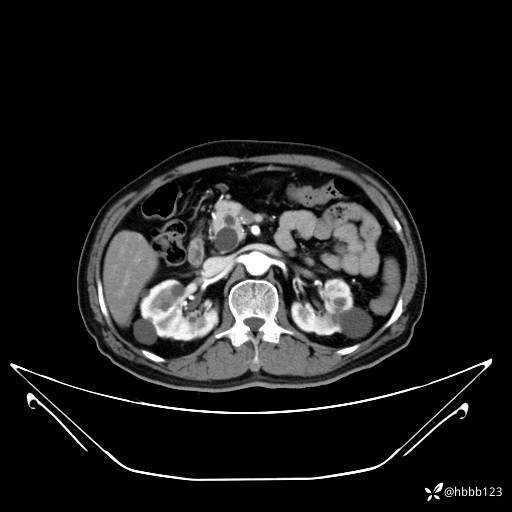

门脉期: